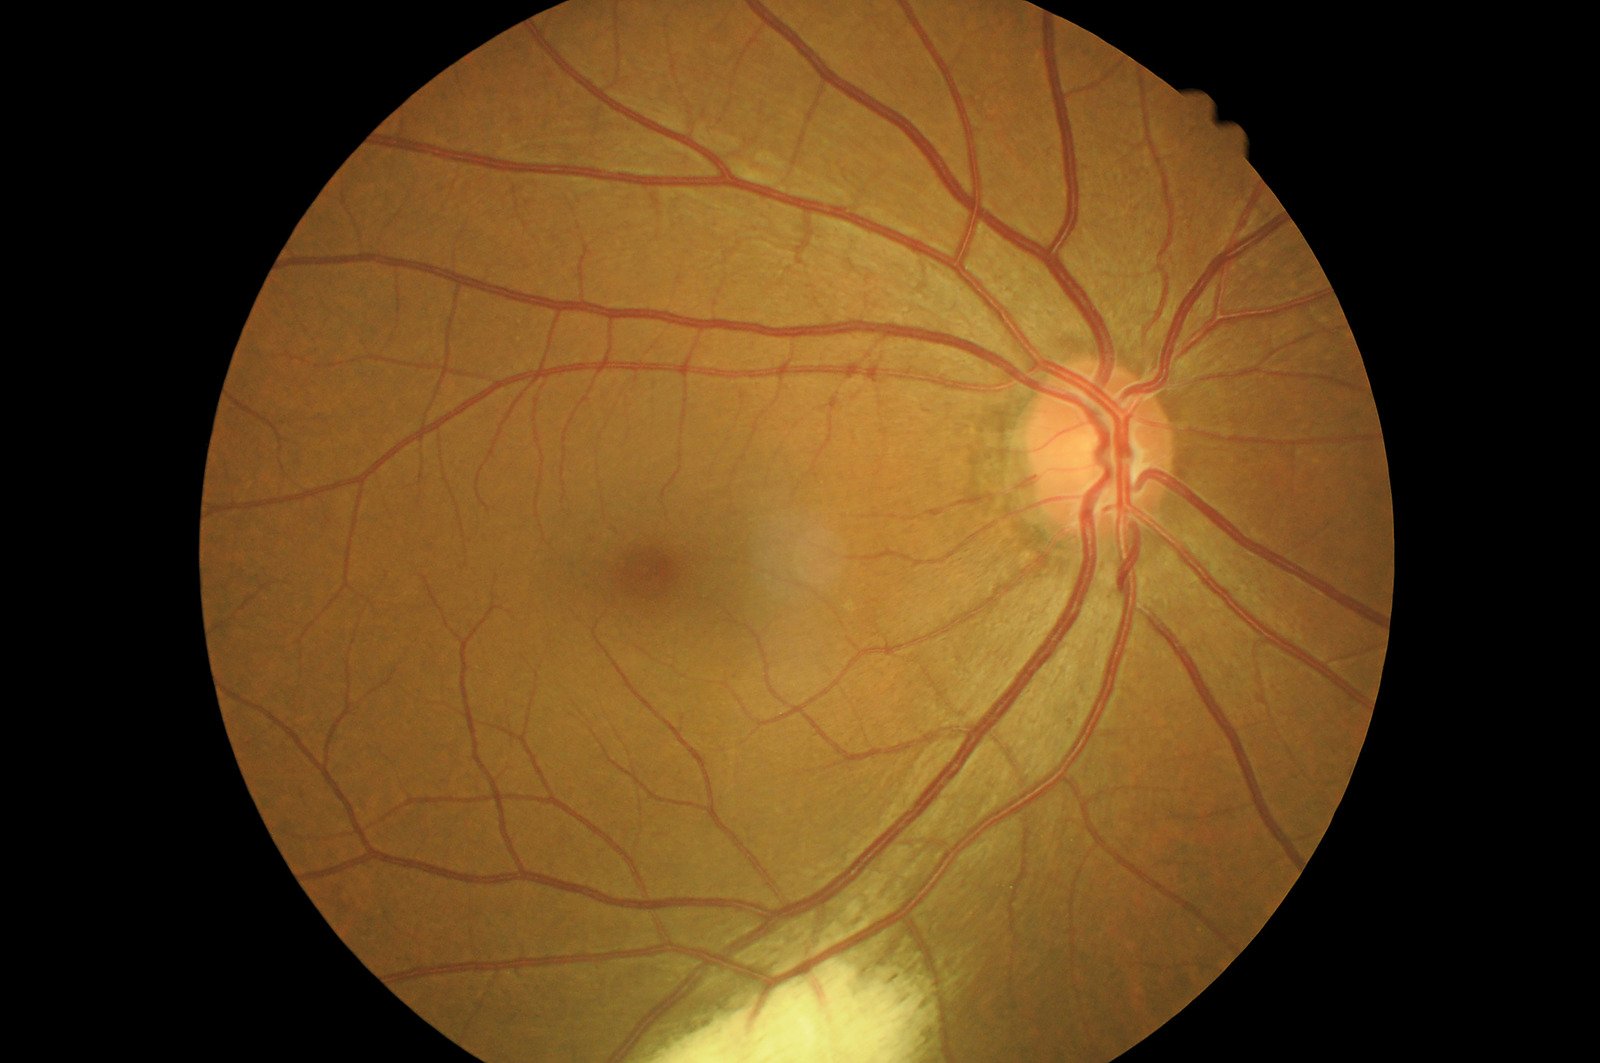

공기 주입술(Pneumatic Retinopexy)은 망막박리(Retinal Detachment)를 치료하기 위한 비침습적 시술 중 하나로, 눈에 공기 또는 가스를 주입하여 박리된 망막을 제자리로 복원하는 방법입니다.

이 치료는 특히 망막박리가 초기 단계일 때 효과적이며, 수술보다 덜 침습적이고 회복 기간이 짧다는 장점이 있습니다.